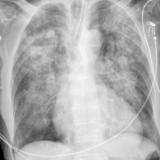

APE 1

Date: 11/05/2005

Views: 4196